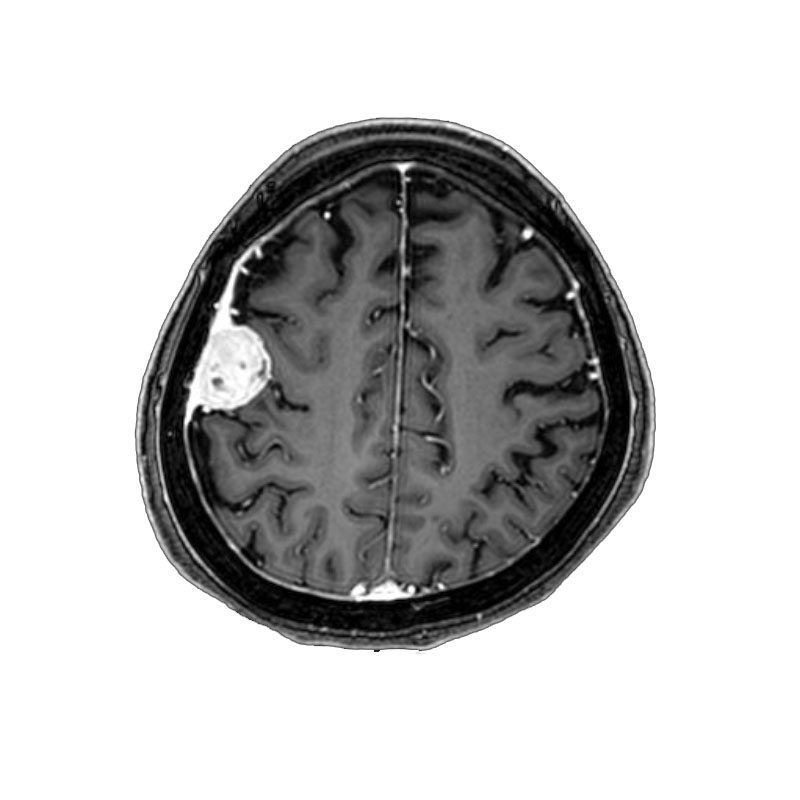

三叉神経鞘腫

摘出術

南田/野本